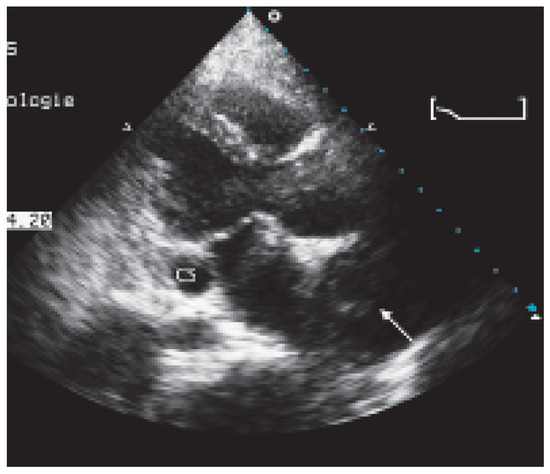

Valve Prosthesis in the Tricuspid Position: An Useasy Relationship

by P. Trigo Trindade, J. Sierra and C. Vuille

Cardiovasc. Med. 2006, 9(4), 167; https://doi.org/10.4414/cvm.2006.01163 - 28 Apr 2006

Case report. A27-year-old woman from Madagascar was referred to our institution because of right heart failure [...] Full article